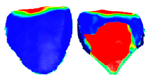

Three-Dimensional Analysis of Posterior Mandibular Displacement in Rats. Lyros I, Ferdianakis E, Halazonetis D, Lykogeorgos T, Alexiou A, Alexiou K-E, Georgaki M, Vardas E, Yfanti Z, Tsolakis AI. Vet Sci 2022;9,144. doi: 10.3390/vetsci9030144. PMID: 35324872.